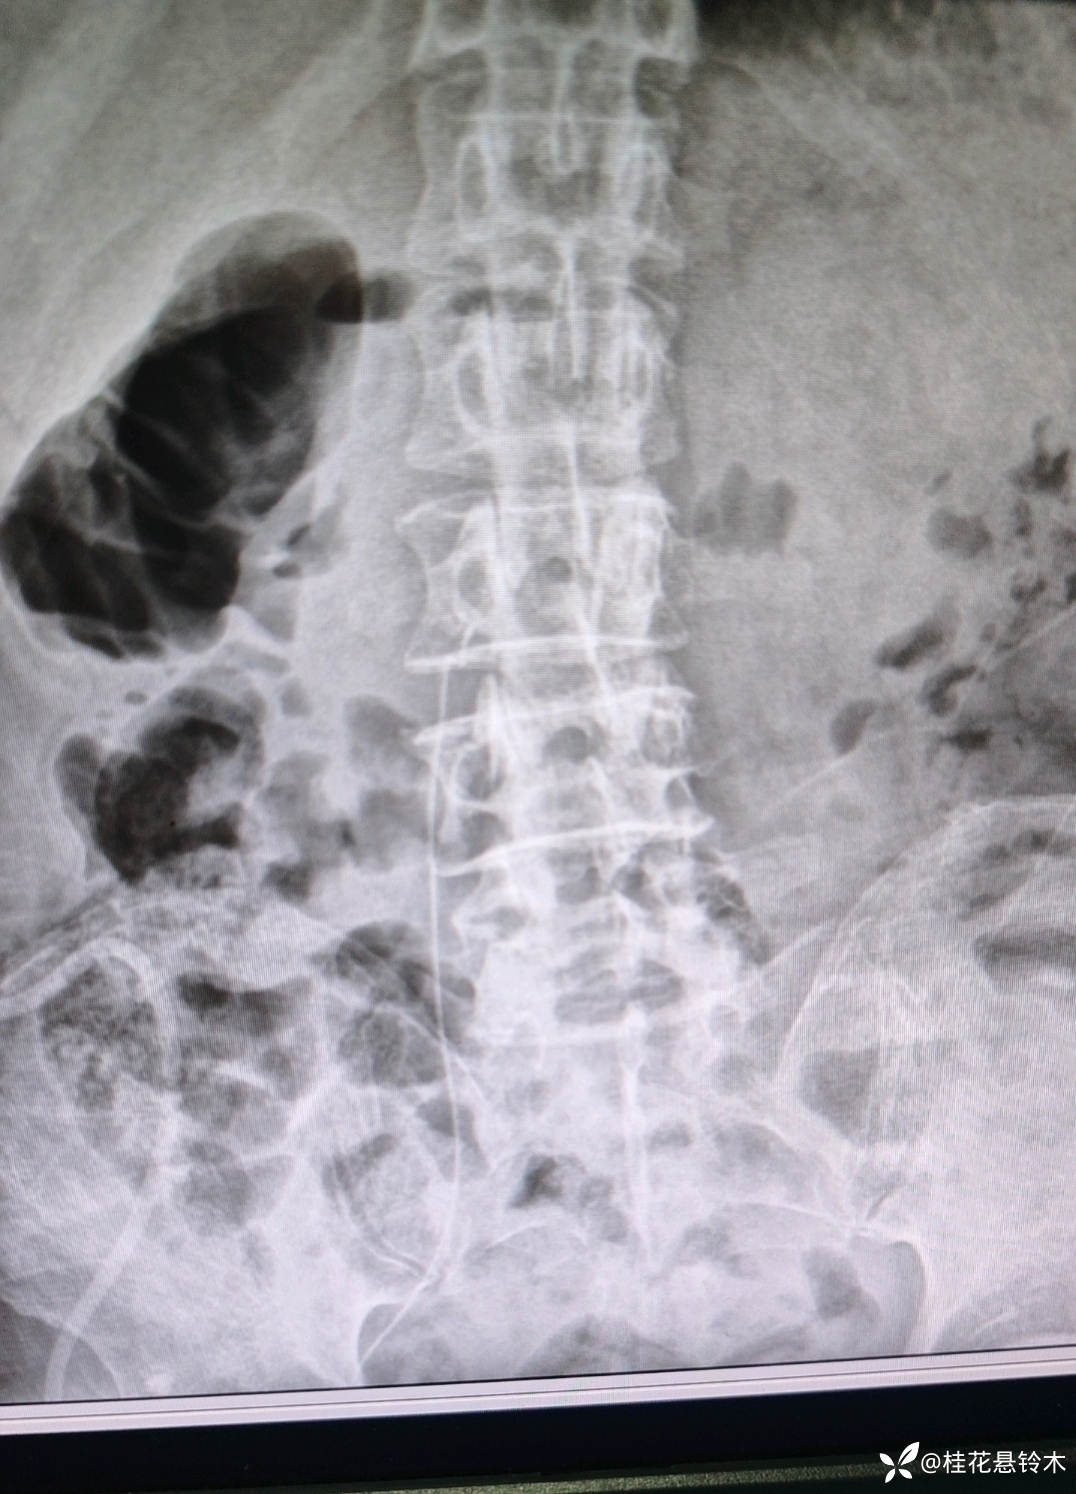

最终汇入下腔静脉:左右两侧的髂总静脉在第4或第5腰椎椎体右前方汇合成下腔静脉,下腔静脉将下肢、盆腔和腹部的静脉血输送回右心房。

此患者因为有上腔静脉综合征,又左侧下肢血栓,故从右侧下肢进入(右侧瘫痪),从大隐静脉置入的中心管路一般都要到腰1才能输液,可是这个到了腰3后一直回弹,太细?在影像科抽出20厘米重新进入好几次也是这样,给家属解释后回病区,没想到,导丝一拔,竟然自己顺利进入了!什么道理?因为病人体质差,没有再去重新拍!回血好!希望一切好!